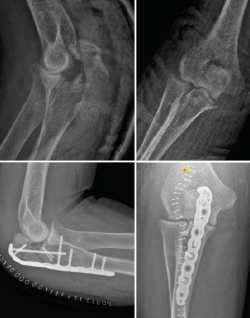

Este patrón de inestabilidad compleja de codo se caracteriza por una luxación posterior de codo asociada a 3 lesiones principales (Figura 14):

• Fractura de la cabeza del radio.

• Rotura del LCL.

• Fractura de la coronoides.

Figura 14. Tríada terrible de codo derecho donde puede apreciarse en las imágenes de tomografía computarizada la fractura de la cabeza del radio, la fractura de la coronoides y la subluxación posterolateral de la ulnohumeral.

Figura 16. Fractura luxación transolecraneana de codo tratada quirúrgicamente mediante la reducción abierta anatómica y fijación interna con placa preconformada de cúbito proximal.

Las placas preconformadas de cúbito proximal son de elección en este tipo de fractura(37,38,39,40). Esto es debido a que nos permiten realizar una reducción anatómica de todos los fragmentos y restablecer tanto la anatomía de la fosa sigmoidea mayor como de la coronoides. En ocasiones, puede ser necesario el uso de injerto óseo para la reconstrucción de la fosa sigmoidea mayor, dado que estas fracturas suelen ser consecuencia de impactos de alta energía y puede encontrarse mucha conminución del foco de fractura(41). Los errores más comunes durante el manejo quirúrgico de estas fracturas-luxaciones son(42):